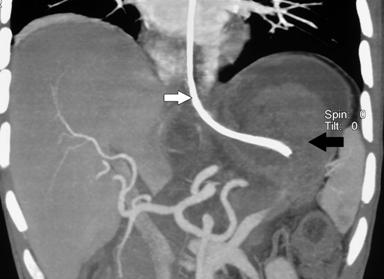

A 32 year old male patient diagnosed as alcohol related acute necrotising pancreatitis (ANP) 2 months ago, now presented with abdominal pain and early satiety. Contrast enhanced computerized tomography (CECT) showed 12 cm walled off pancreatic necrosis (WOPN) (Figure 1). Endoscopic ultrasound (EUS) revealed large WOPN and power doppler revealed vascularity in collection with pulsatile flow suggestive of blood leaking into collection (Figure 2). However, no abnormal vessel or pseudoaneurysm could be identified. CT angiography (CTA) also showed normal major abdominal arteries (Figure 3). Since patient was symptomatic, after informed consent EUS guided transmural drainage was attempted. Now there was no vascularity in collection and procedure was successfully accomplished. A 7 Fr nasocystic drain (NCD) was inserted and it drained purulent material. Patient had marked symptomatic relief but 6 hours later had severe pain and hematemesis with blood coming through NCD also. CTA revealed blood in WOPN but no abnormal bleeding vessel was identified (Figure 4). Digital subtraction angiography (DSA) also did not reveal any abnormal or bleeding vessel. The patient was managed with blood transfusion and NCD was kept patent by intermittent flushing. The bleeding subsided and the effluent from NCD cleared in 48 hours. The NCD was replaced with 10 Fr pigtail stents and CT abdomen done 3 weeks later revealed resolution of WOPN (Figure 5). The patient has been asymptomatic over a follow up period of 13 months.

Figure 4. Hyperdense contents suggestive of blood seen in the collection (black arrow). NCD also seen in the collection (white arrow). |